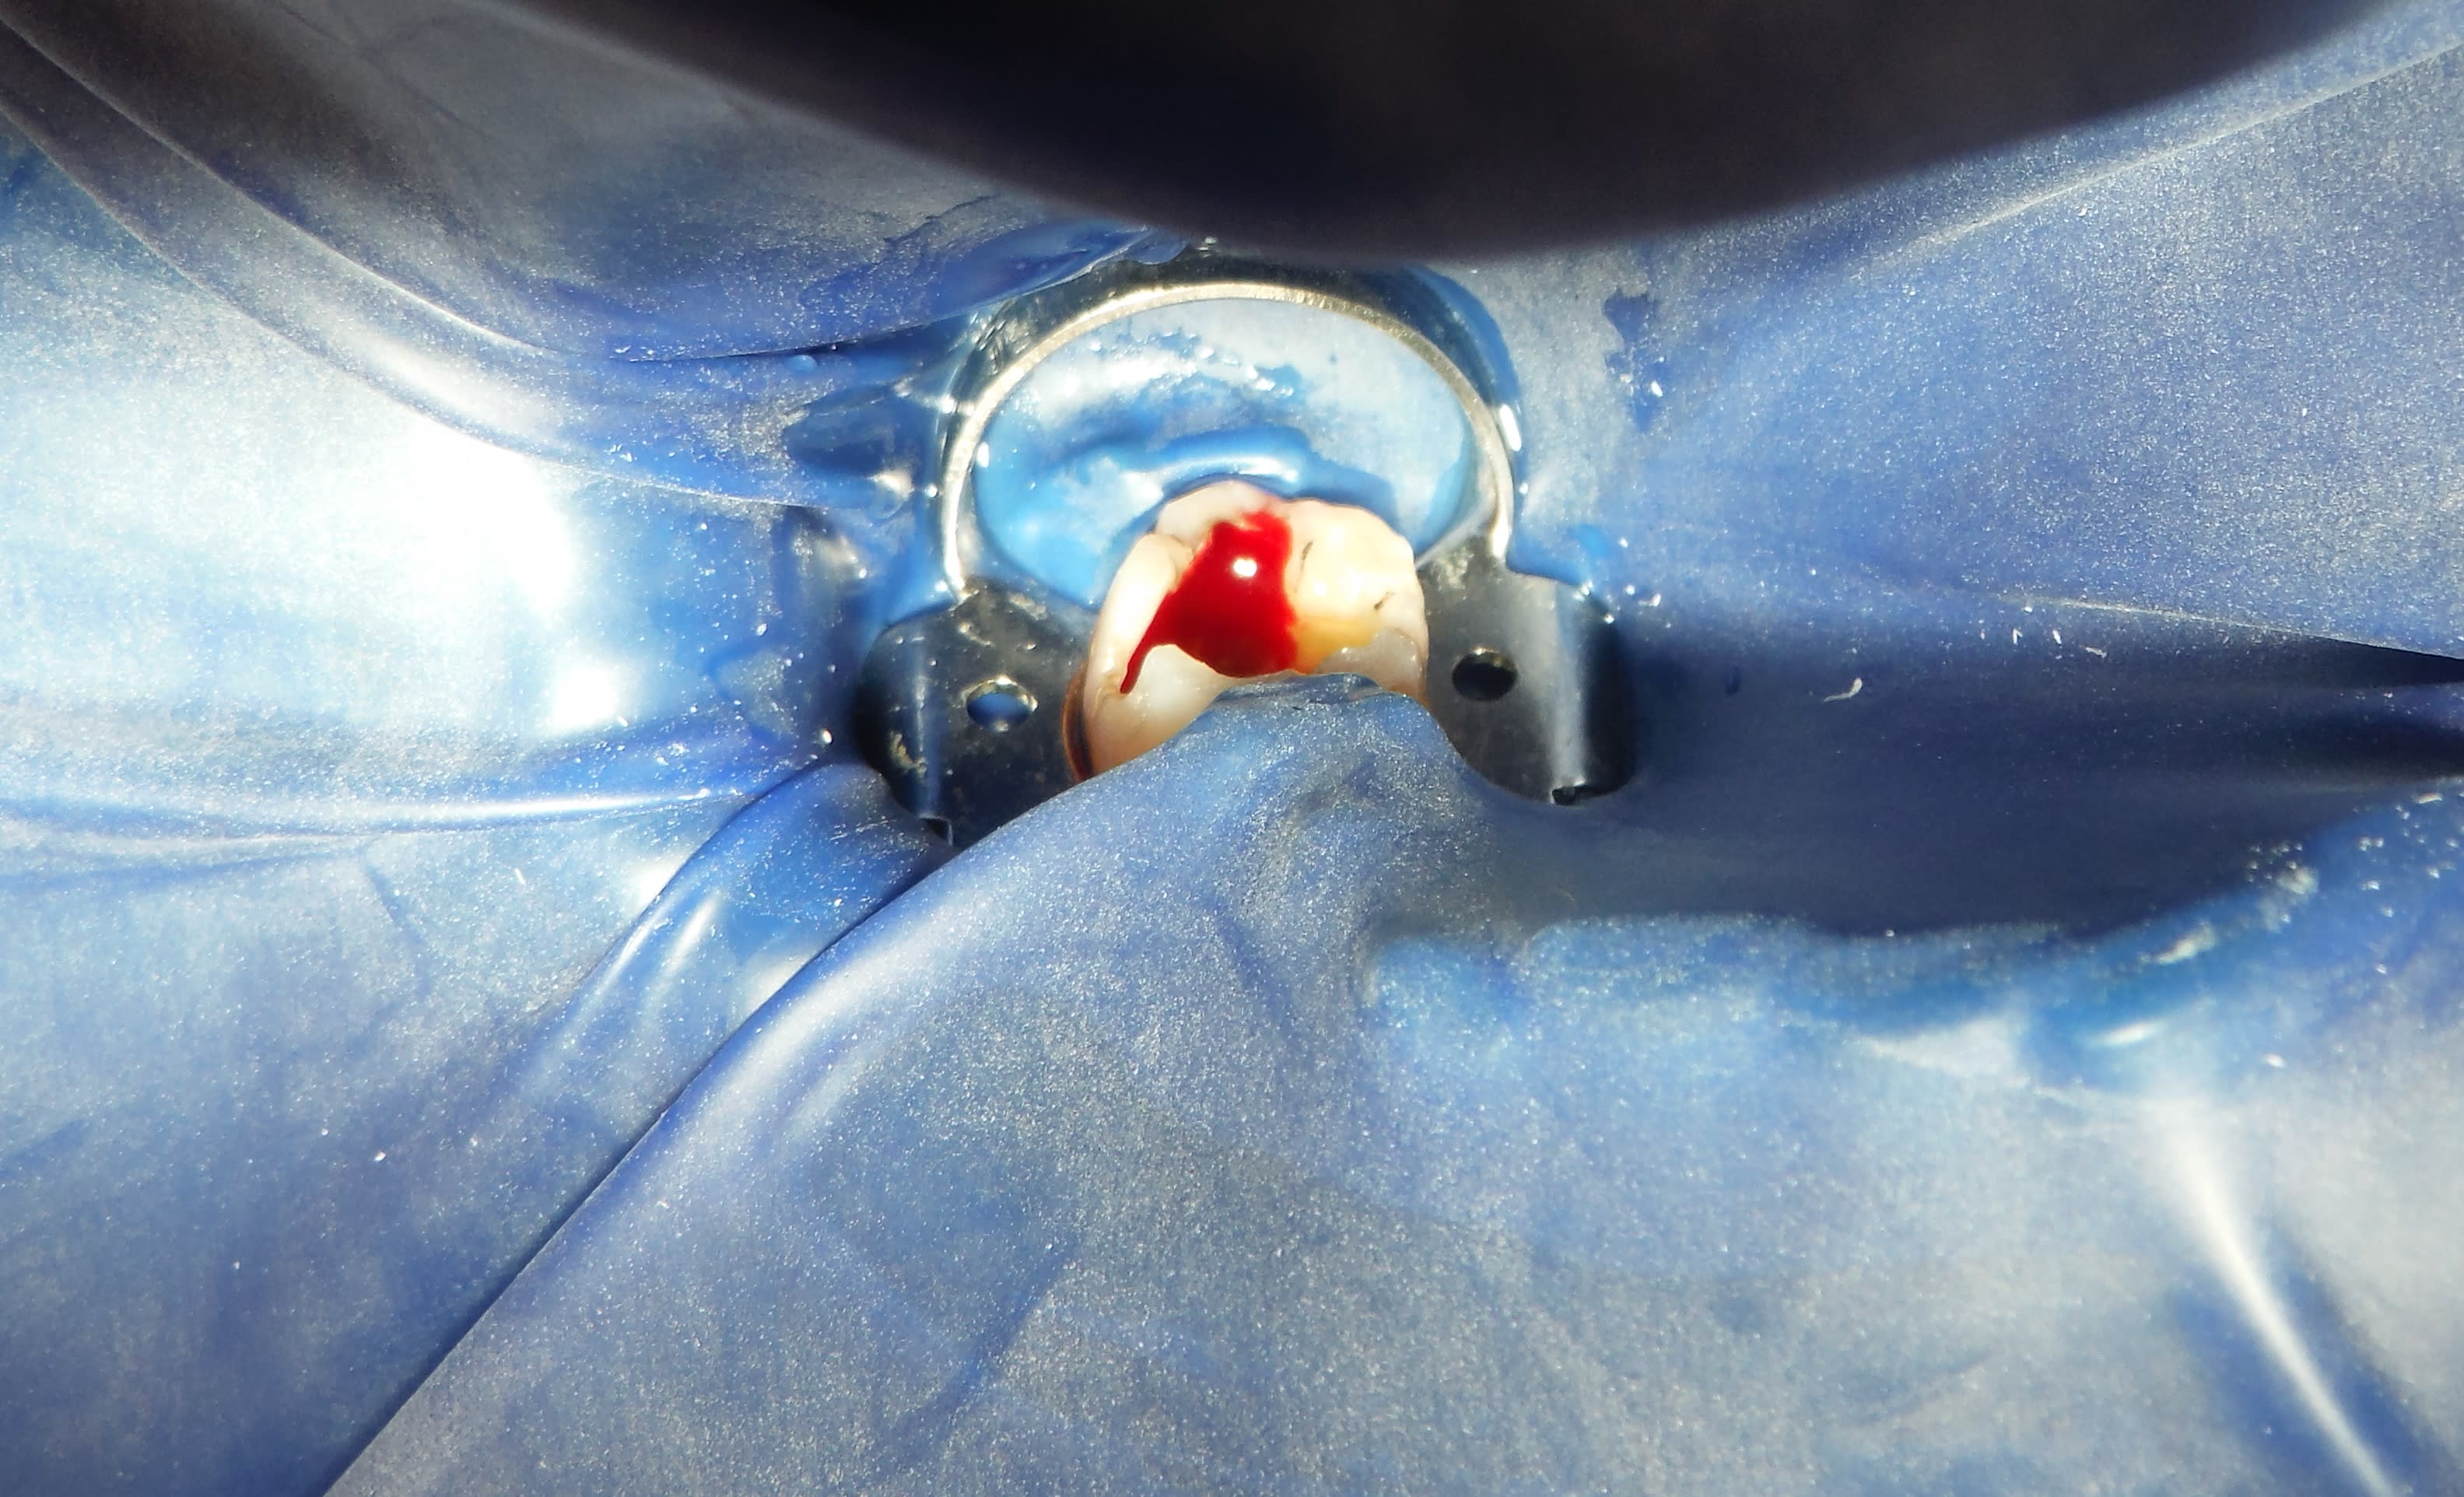

pour le coup c'était courbe (il faut de bons yeux désolé!-)

Dscf2566 2 o3kxaw - Eugenol

Dscf2566 3 qkcvb1 - Eugenol